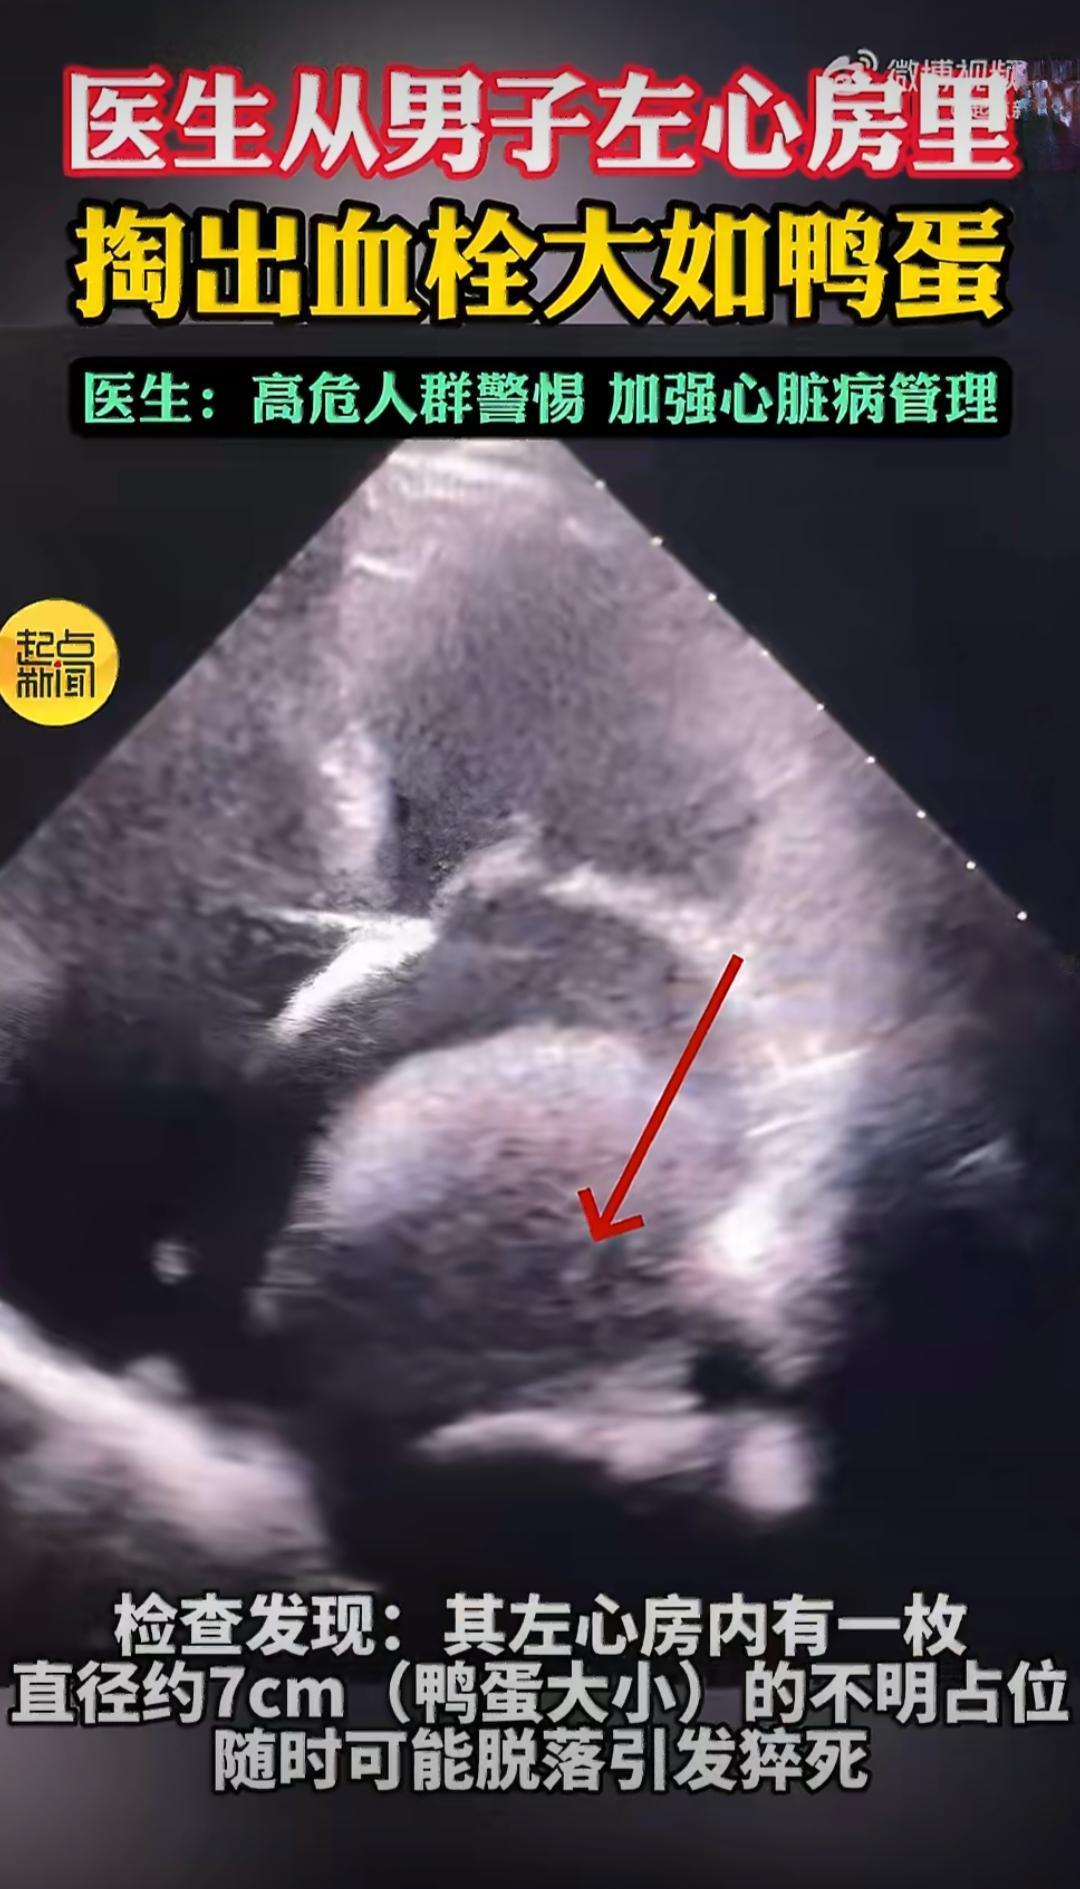

58岁的王先生之前得过脑梗,身体一直带着后遗症,右侧肢体活动不太方便,一次意外摔倒后,他到西安市人民医院做检查,原本只是排查摔倒带来的身体损伤,没想到心脏检查结果让医生都捏了一把汗,心脏彩超显示他的左心房里有一个直径差不多7厘米的不明占位,大小和鸭蛋差不多,这个不明物体牢牢待在心脏里,随时都有可能脱落,一旦掉下来顺着血液流动,要么堵住脑血管引发更严重的脑梗,要么直接堵塞心脏瓣膜,瞬间造成猝死,相当于心脏里藏了一颗随时会引爆的定时炸弹。医生结合王先生的病史和进一步检查,很快确定这个占位是巨大血栓,同时还发现他存在二尖瓣严重狭窄的问题,心脏瓣膜的异常让血液在左心房里长期淤滞,这也是血栓慢慢长到这么大的主要原因,而且这枚血栓尺寸达到73×60毫米,还和心房后壁粘连紧密,手术难度和风险都非常高。为了尽快拆掉这颗致命炸弹,医院组建多学科团队制定周密手术方案,紧急为王先生开展取栓手术,整个手术过程持续了三个半小时,医生小心翼翼地将这枚巨大的圆形血栓完整剥离取出,同时还处理了病变的二尖瓣,解决了血栓形成的根源问题。手术顺利完成后,王先生的身体恢复得很不错,没有出现并发症,在医院休养一段时间后就顺利出院了。很多人不知道,左心房血栓大多没有明显症状,平时很难察觉,像王先生这样通过意外检查发现的情况并不少见,这类血栓的高危人群主要是有房颤、心脏瓣膜病、脑梗病史的人,血液流动异常容易在心房内形成血栓。医生也针对这件事给出提醒,想要预防左心房血栓,核心就是做好高危人群的长期规范管理,坚持抗凝治疗,同时定期监测心脏状况,把心脏基础病控制好,从源头减少血液淤滞和血栓形成的可能,避免这类隐匿的心脏风险突然引发致命意外。脑梗 脑梗死 【